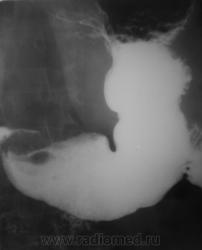

1. Аденоидные полипы в антральном отд. желудка.

Во всяком случае полиповидное выпячивание в антруме налицо, но думаю оно подслизистое... А варикоз - явно не виден, есть в кардии складка небольших размеров, но явно в глаза она не бросается, хотя складки везде толстоваты...

полиповидные образования в антральном отделе +грыжа ПОД

Смею предположить (с учетом наличия + тени кардии желудка по верхне-медиальной стенке, некоторого удлинения и выпрямления кардиального канала, неровности контуров) кардио-эзофагеальный рак без стеноза. В антруме - полипы. Вряд ли подслизистые образования, такие на вершине складок не образуются.

На снимке который поместил Анатолий Владимирович, м.б. или ГПОД (кардиальная) или ахалазия пищевода,при ней газовый пузырь отсутствует или уменьшен в размере. А м.б. и c-r пищеводно-желудочного перехода.

Наблюдение архивное. Я этот снимок привел как типичный пример ампулы пищевода, нормальной, в горизонтальном положении тела, которую наша братия, почти поголовно принимает за грыжу пищеводного отверстия, и соответственно с нашей подачи хирурги пытаются это оперировать...

1.о варикозе вен н\трети пищевода стоит подумать, весьма коварная вещь;

2. полипы препилорического отдела не вызывают сомнения, но что тут интересно - картинка то меняется, периодически крупный дефект выполнения как бы исчезает...но появляется в основании луковицы - сдается мне - это полип на длинной ножке, вот и гуляет он через привратник туда-сюда, вспоминайте - симптом "собачки на цепочке"...

Да, данные ФГДС подтвердили наличие полипов в препилорической части, один действительно - "гулящий" - на длинной ножке.